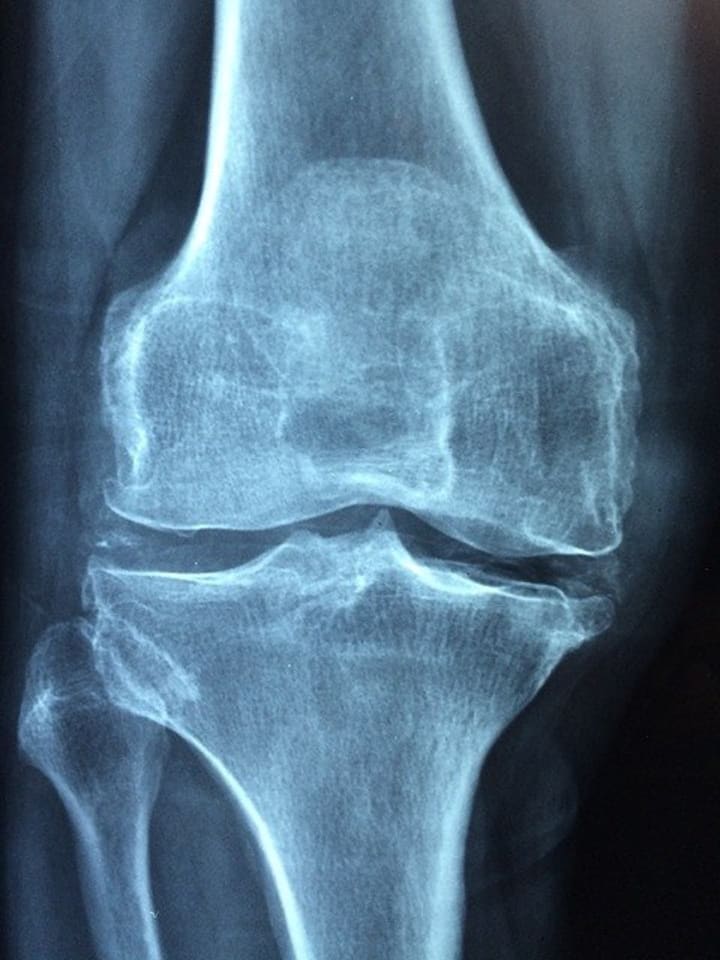

6. Osteoporosis

When it comes to sedentary habits, this health risk isn't one of the apparent ones. Physical lack of exercise compromises your bones and might lead to osteoporosis.

Another reason osteoporosis is an outcome of an inactive way of life is the lack of sunlight. Less sunshine indicates less vitamin D, which has an unfavorable influence on the strength of your bones.